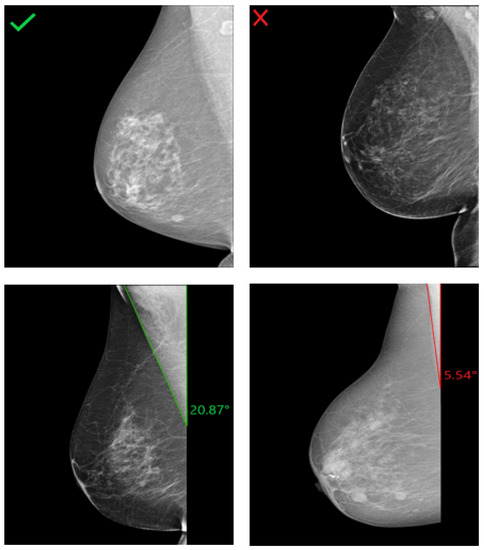

In an adequately positioned mammogram, the pectoralis muscle margin should be well visualized, triangular, or slightly concave with an angle >10°. These criteria are required to visualize the maximum amount of breast tissue on the clinical images. With decreasing angle, the risk of missing relevant breast tissue parts for mammographic cancer detection increases. Examples of R-MLO views with correct and inadequate pectoralis muscle angle are shown in Figure 16.

Figure 16. Assessment of the pectoralis muscle angle in four different R-MLO views. (Left): Mammograms with correct pectoralis muscle angle. (Right): Inadequate positioned mammograms due to convex pectoralis muscle (above) and angle <10° (below).